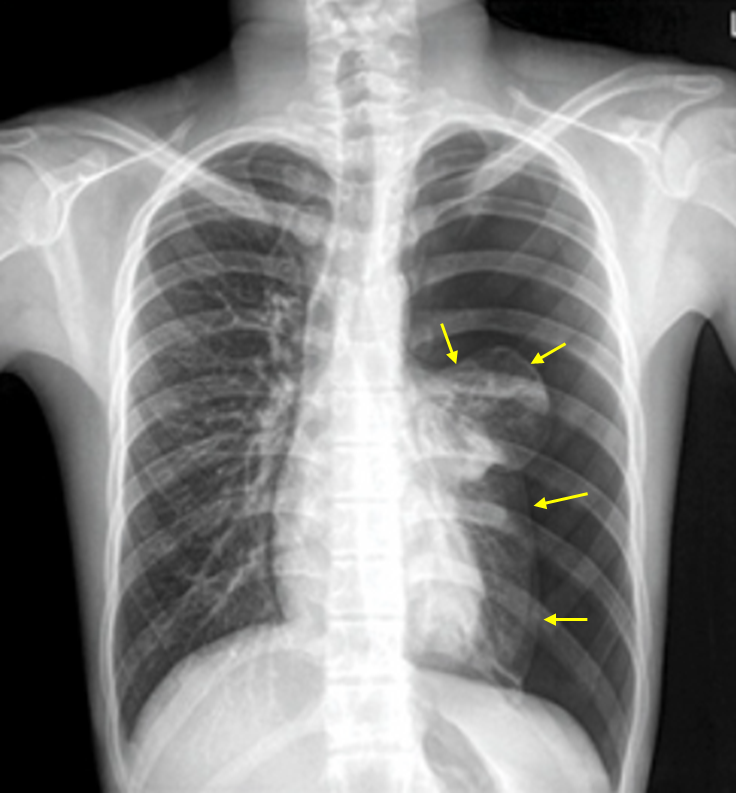

15세 남자가 3시간 전부터 갑자기 가슴이 아프고 숨쉬기가 힘들어서 응급실에 왔다. 가슴청진에서 왼쪽 호흡음이 감소하였다. 가슴 X선 사진이다. 치료는?

Img | CXR: 좌측 폐 pleural line |

Imp: 일차성 자발성 기흉(primary spontaneous pneumothorax, PSP)

기흉의 양이 매우 크므로 흉관 삽입을 시행한다.

• CXR에서 좌측 폐에 pleural line이 보이며, 특이 병력이 없으므로 일차성 기흉으로 진단할 수 있다.

• 기흉이 좌측 폐의 대부분을 차지하고 있으므로 경과관찰, 산소흡입, 바늘흡인보다 흉관 삽입을 먼저 고려할 수 있다.